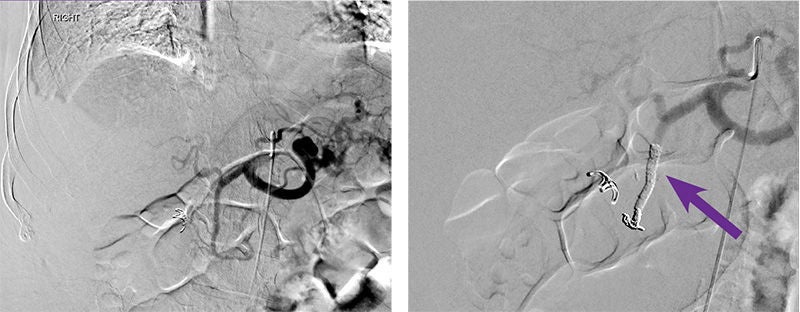

Gastroduodenal artery (GDA) embolization

Courtesy of Dr. Gary Siskin I Albany Medical Center

Intervention used

Arterial access was gained via the right common femoral artery. A Sos-2 catheter was positioned at the origin of the celiac axis and an angiogram was performed, which failed to demonstrate any abnormalities of the gastroduodenal artery (GDA). This was confirmed after selective catheterization and angiography of the GDA with a Renegade™ HI-FLO™ Microcatheter. Prophylactic embolization of the GDA was then performed with two 4 mm X 15 cm Embold™ Detachable Coils followed by administration of 0.5 mL of Obsidio Embolic (purple arrow). Follow-up angiography demonstrated successful occlusion of the GDA.

Purple arrows pointing to administration of 0.5 mL of Obsidio Embolic.